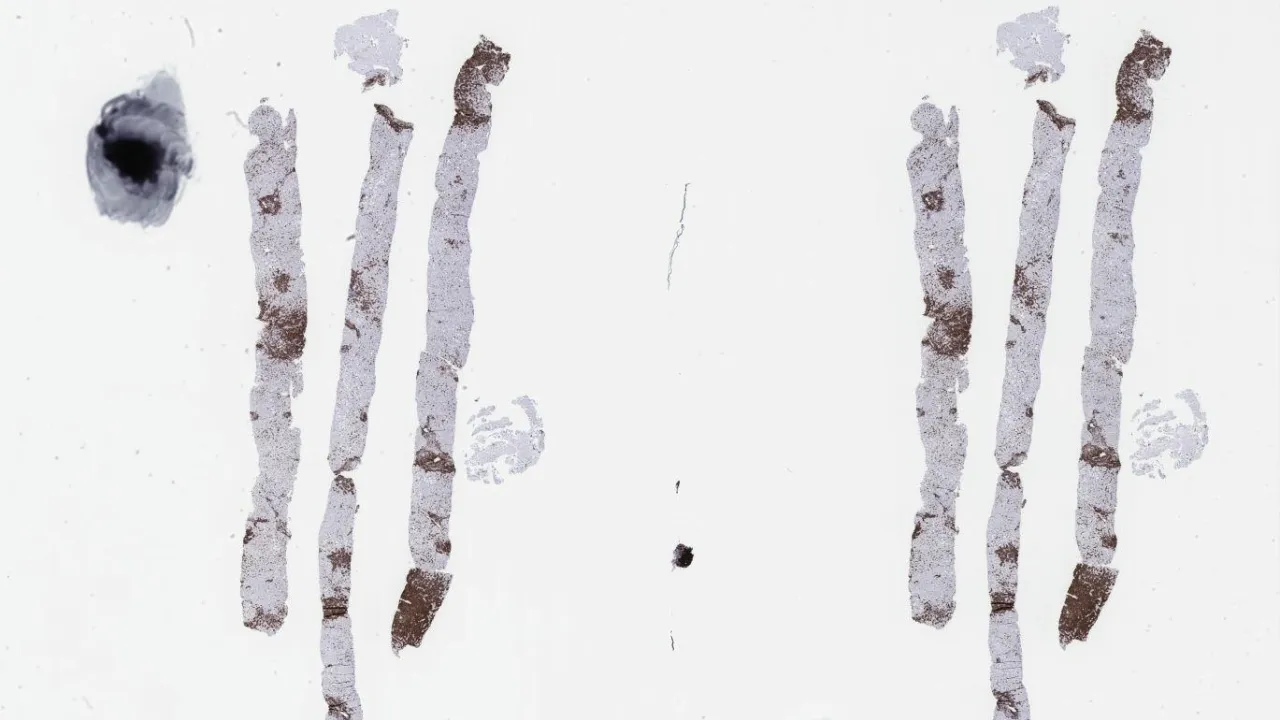

Lung, Talc granulomata